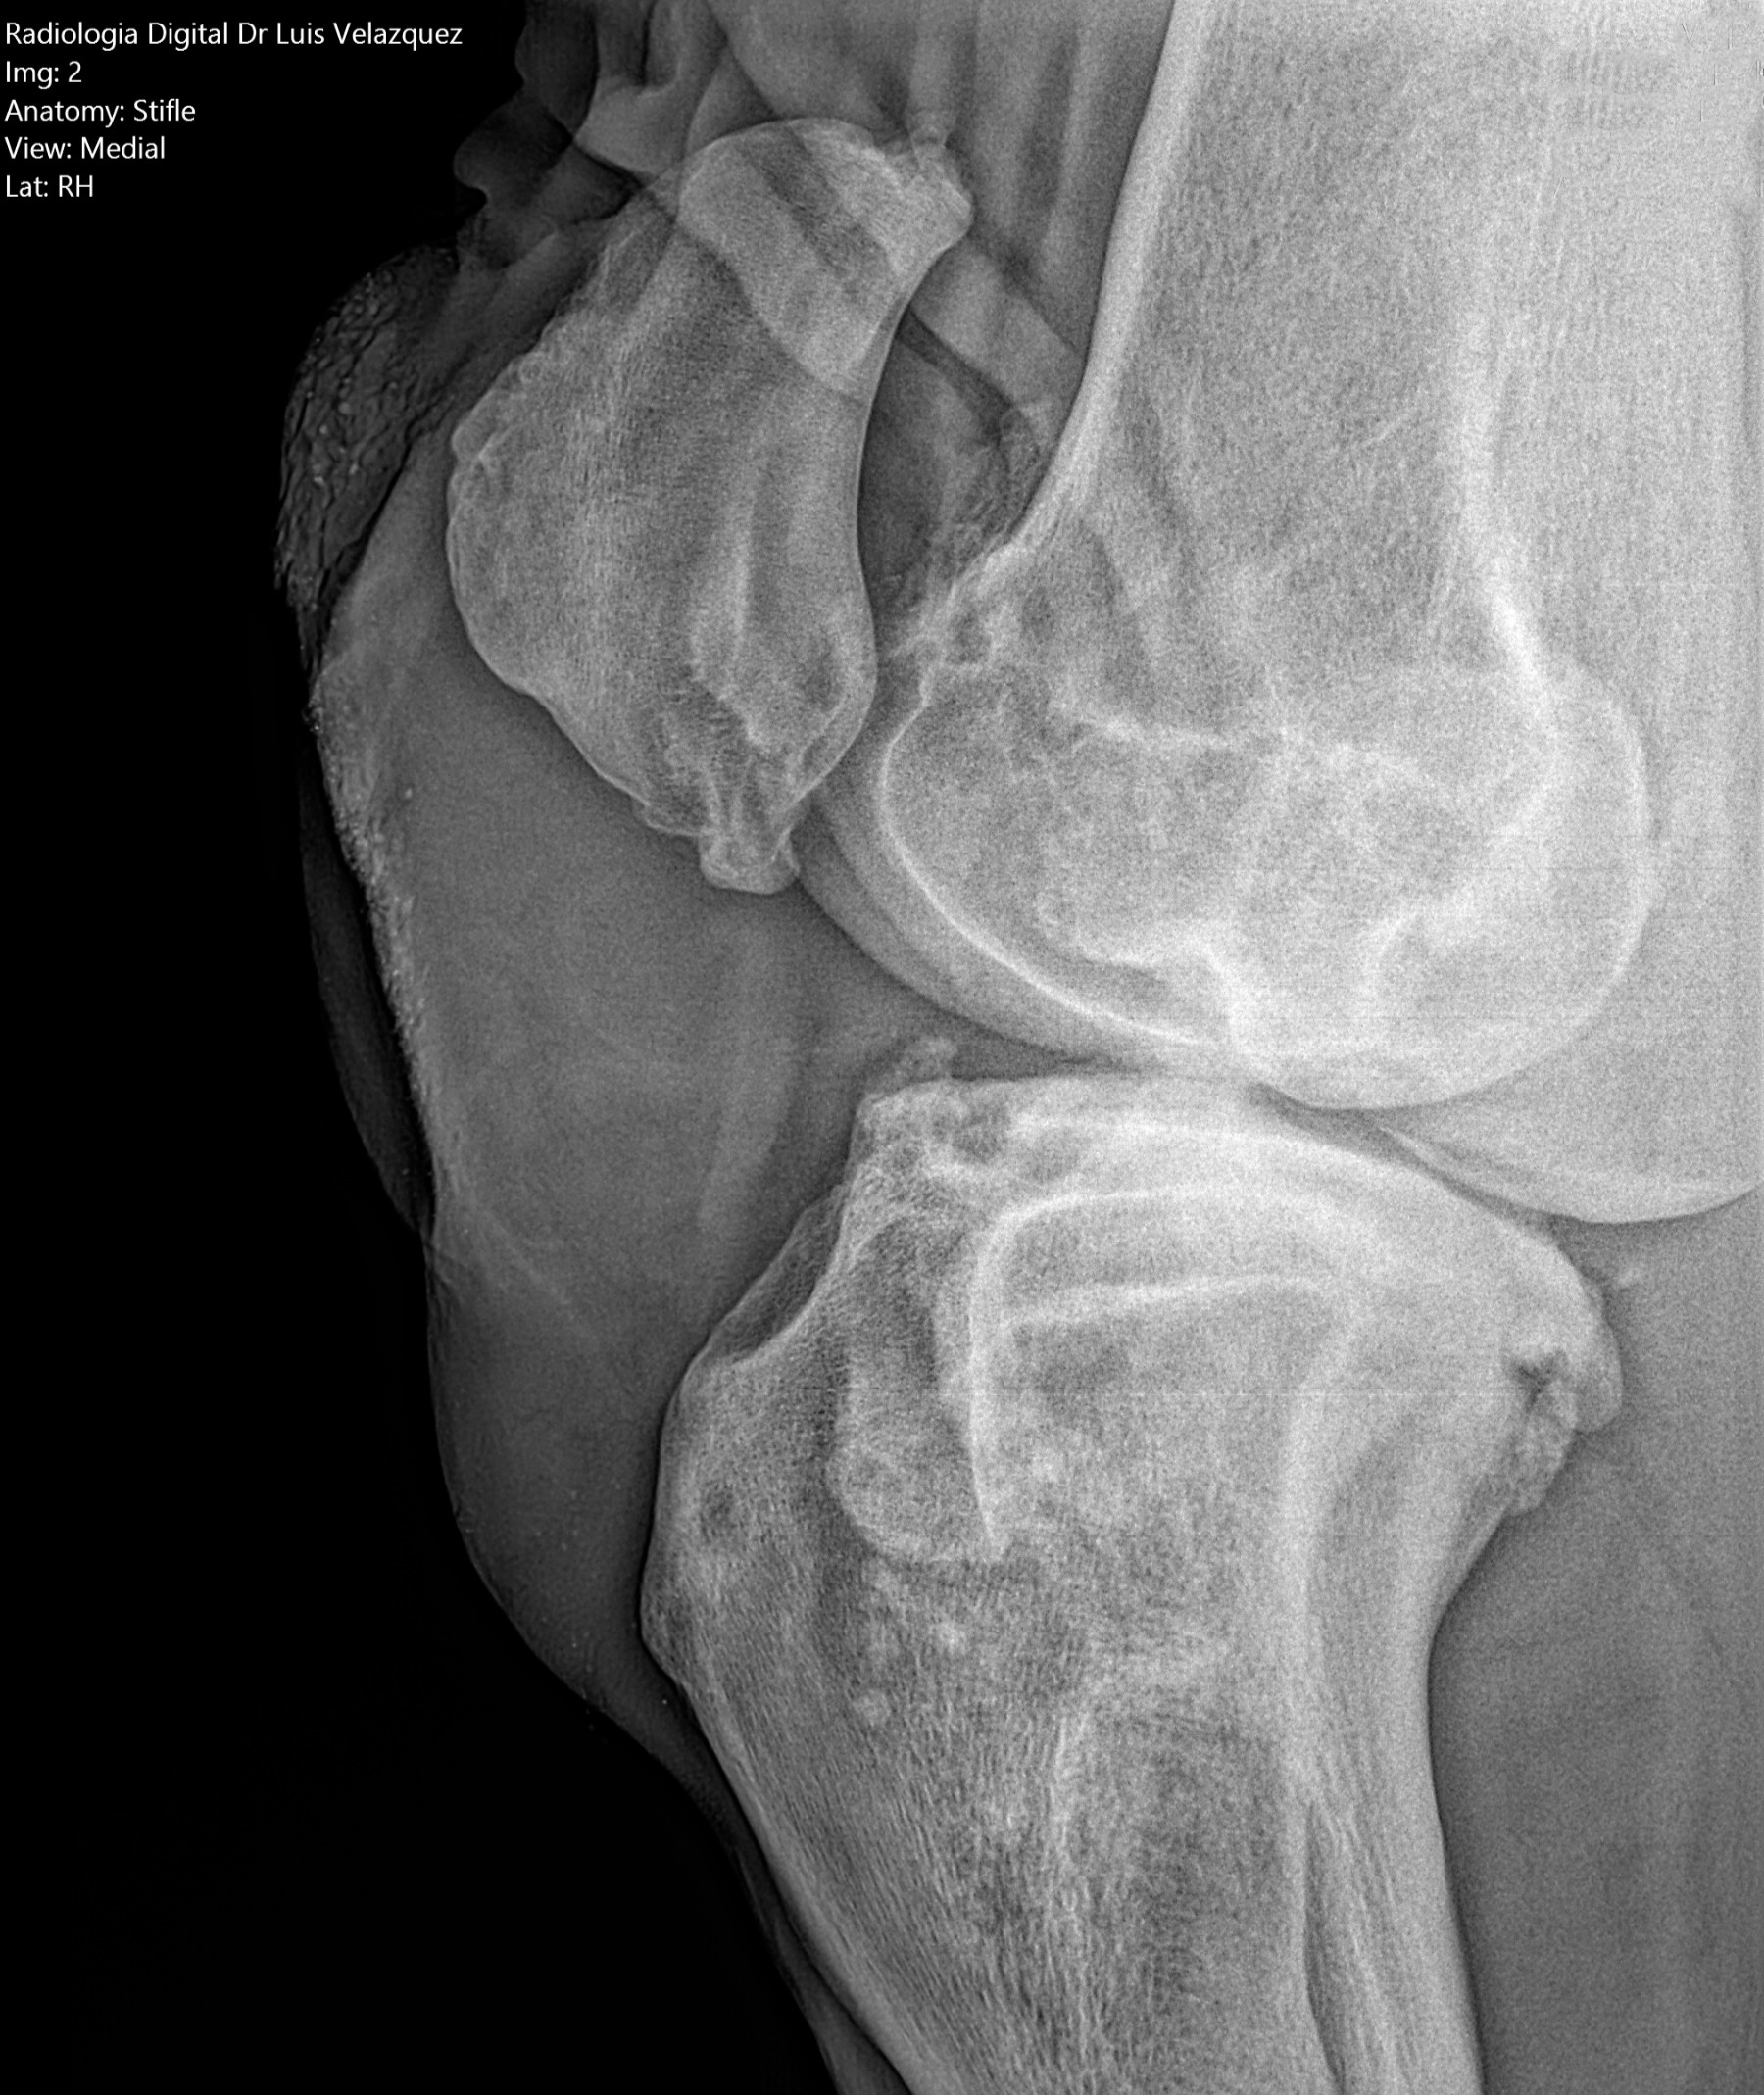

Cambios Térmicos en las Extremidades de Caballos,

Asociados a Golpes y su Evaluación por Termografía.

Los caballos de salto, en competencia, pueden derribar obstáculos y lastimarse. Si se golpean, no siempre claudican. Considerando al calor como un signo de inflamación, se evaluaron los cambios térmicos de 6 áreas de las extremidades torácicas y pelvianas de 23 caballos de salto en nivel de competencia de 1.05 a 1.60 m de altura, por medio de termografía durante 4 días de competencia (N=2208 áreas).